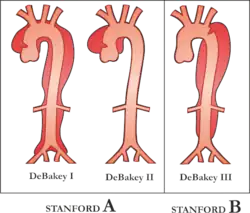

The artery wall is composed of three concentric layers: the intima, media and adventitia. In general, an arterial dissection is a tear in the innermost layer of the arterial wall that makes a separation which allows blood to flow, and collect, between the layers. Arterial dissections include: an aortic dissection (aorta), a coronary artery dissection (coronary artery), two types of cervical artery dissection involving one of the arteries in the neck – a carotid artery dissection (carotid artery), and a vertebral artery dissection (vertebral artery), a pulmonary artery dissection is an extremely rare condition as a complication of chronic pulmonary hypertension.[13]

Whereas cardiac surgeons are usually in charge of managing type A dissections, type B dissections are typically managed by vascular surgeons. The most common risk factor for type B aortic dissection is hypertension. The first line treatment for type B aortic dissection is aimed at reducing both heart rate and blood pressure and is referred to as anti-impulse therapy.

Should initial medical management fail or there is the involvement of a major branch of the aorta, vascular surgery may be needed for these type B dissections. Treatment may include thoracic endovascular aortic repair (TEVAR) with or without extra-anatomic bypass such as carotid-carotid bypass, carotid-subclavian bypass, or subclavian-carotid transposition.[14]